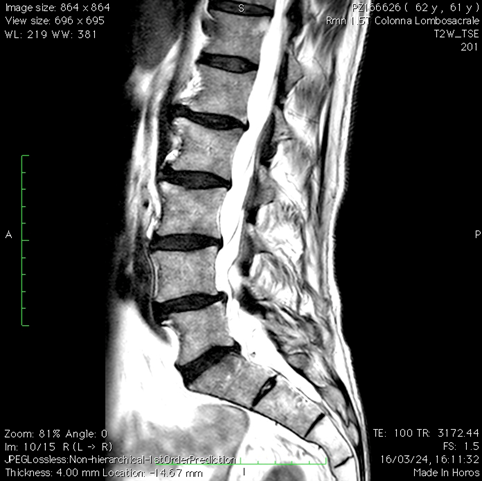

Risonanza magnetica lombare pre-operatoria

Intervento chirurgico eseguito:

PROCEDURA PLIF: POSTERIOR LUMBAR INTERBODY FUSION

Stabilizzazione vertebrale percutanea L4-L5 + introduzione di cage intersomatica PLIF Radiografia lombare post-operatoria